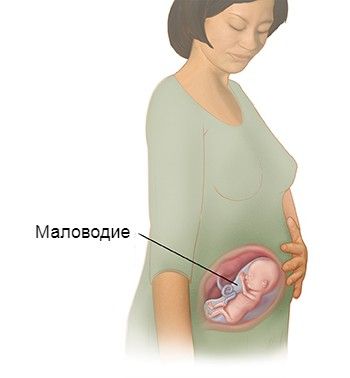

Амнион и Околоплодные Воды: Функции и Роль в Беременности